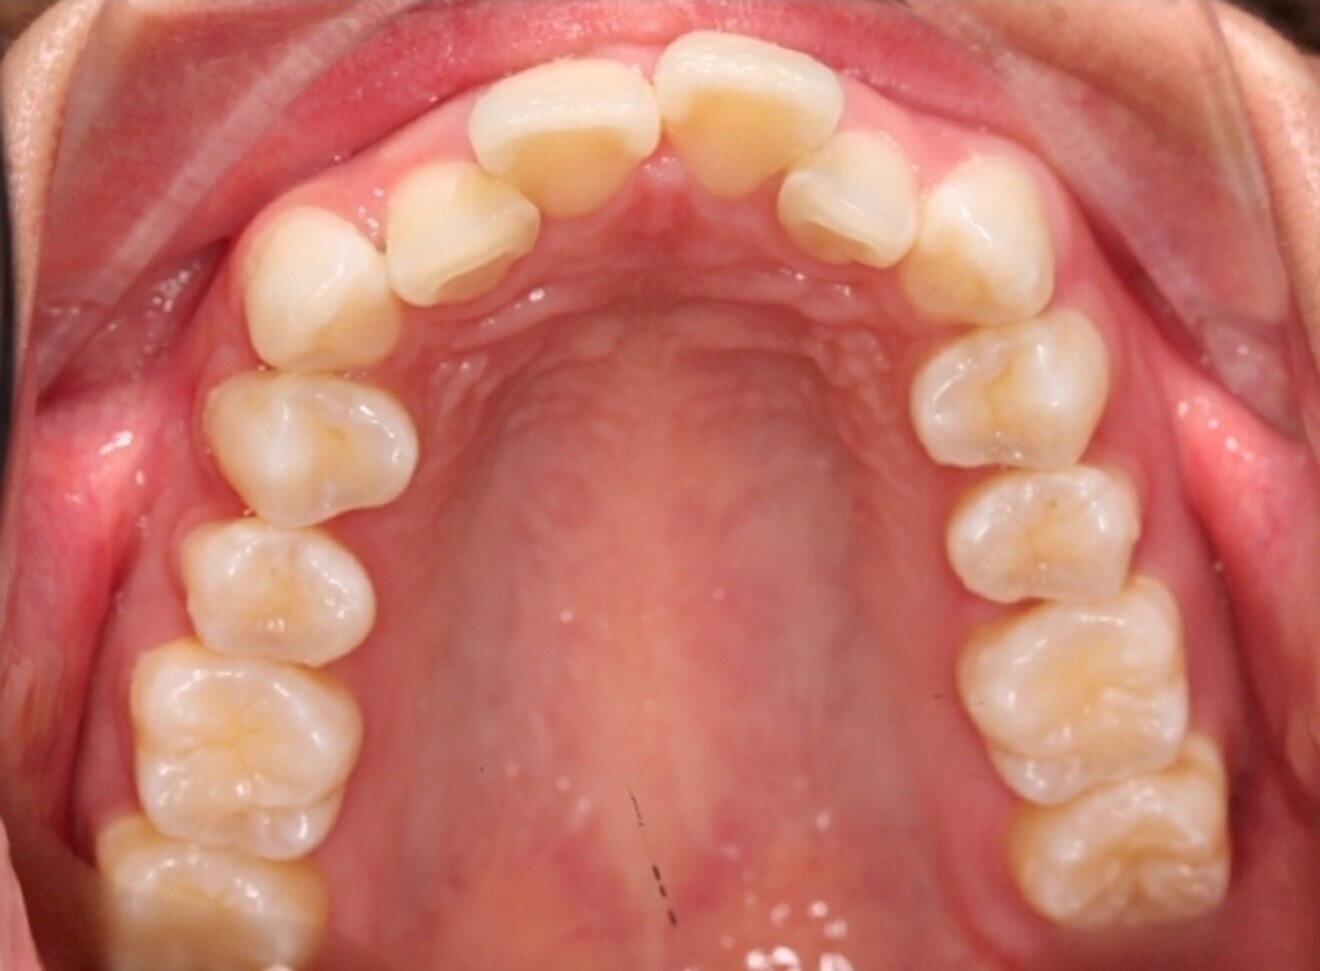

The starting point for Oratomic4D was selecting a real patient to replicate. After an extensive search, the patient, Tina, was chosen for her ideal oral anatomy and range of treatments that could be simulated. Unlike a typodont model, Tina had mild crowding, impacted maxillary and mandibular third molars, and complex root canal anatomy (Figs. 2–7).

These irregularities in Tina’s oral anatomy made her an ideal candidate for the creation of a range of realistic simulation models that are highly representative of the types of patients encountered in dental practice.